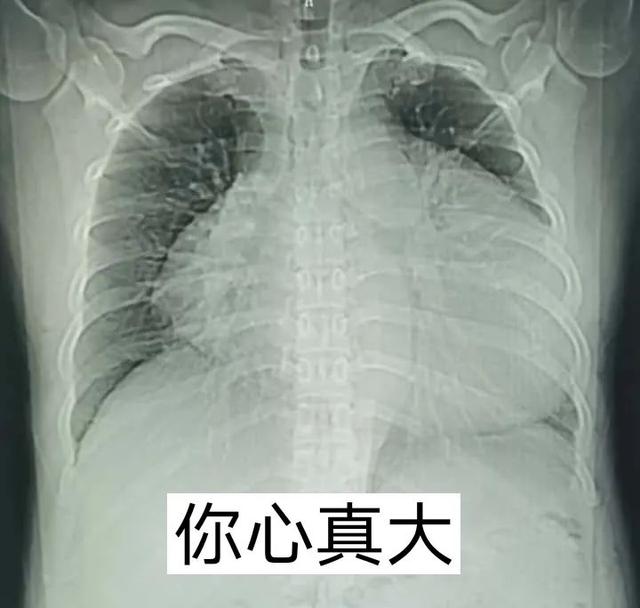

(图为两例大量心包积液患者胸部正位片,心影明显增大)